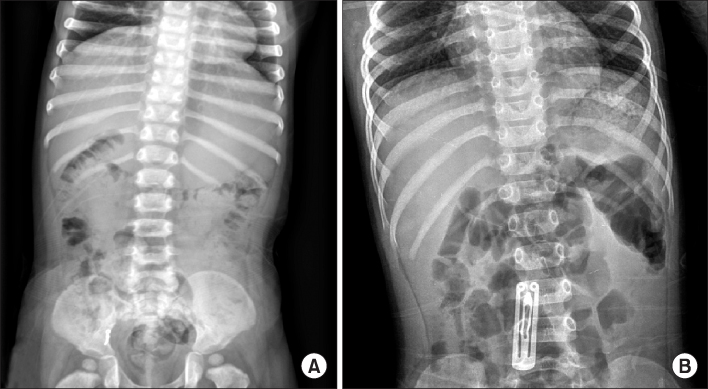

Fig. 3.

(A) Perforation of duodenal second portion by hair pin. (B) Perforation of gastric greater curvature and jejunum by two magnets.

Fig. 3. (A) Perforation of duodenal second portion by hair pin. (B) Perforation of gastric greater curvature and jejunum by two magnets.